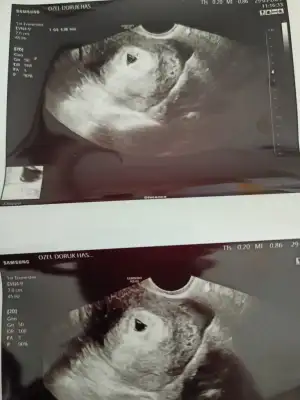

Günaydınnn kızlarr bugün çok şükür kesemizi gördük vajinal muayneyle hayırlısıyla 2 hafta sonra kalp atıslarınn duymak icin gidicez şimdi 2 hafta bekleki geçsin zaman :)

Gözünaydın canım. Bnm de kesem dün net şekilde gözüktü. Dr perşembe çağırdı. Cuma yokum dedi. Haftaya kalp atışını duyabiliriz herhalde. Sizi neden 2 hafta sonra çağırdı ki.

Eklentiler

• 16222752427917197591779440385290.webp

16222752427917197591779440385290.webp

29,8 KB · Görüntüleme: 84